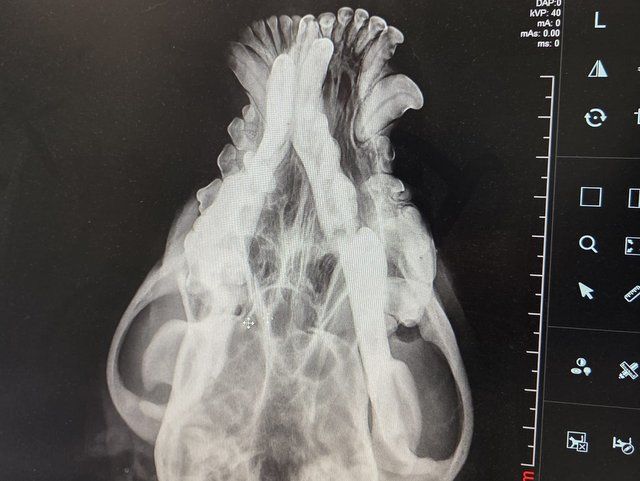

Röntgenbilder zeigten das Ausmaß der Zerstörung des Unterkiefers und den Bruch eines Beines.

Dieser Hund muss grausame Schmerzen haben, Zähne sind aus der Verankerung gerissen und sein Gesichtsschädel ist nicht mehr symmetrisch. Ein großes Stück des Unterkiefers ist komplett abgebrochen.

Es braucht sicher viel Geschick, um das wieder so zusammenzusetzen, dass der Hund später problemlos fressen kann.

Camush Kopf ist wieder symmetrisch, der Kiefer wird jetzt mit Platte und Verdrahtung zusammengehalten und ein paar Zähne fehlen jetzt.